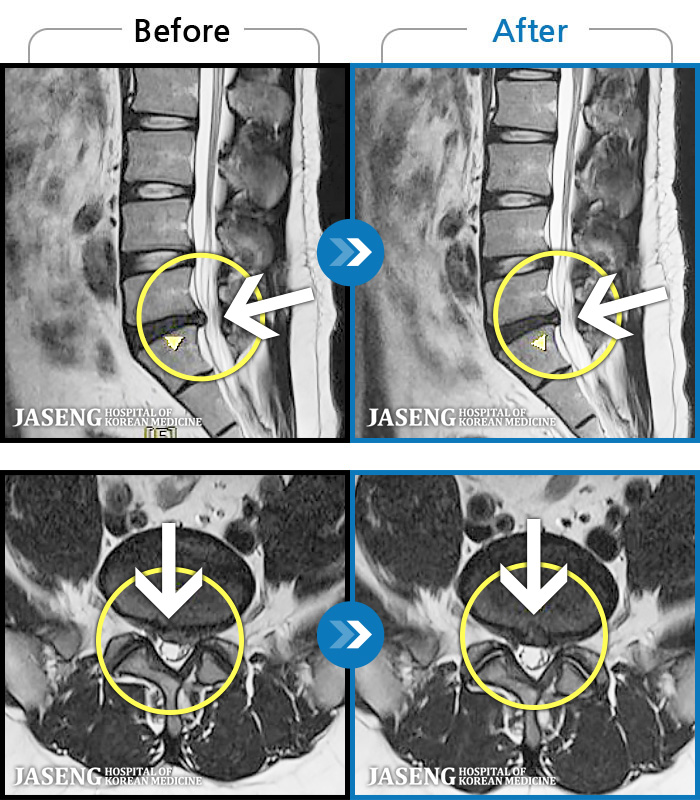

[] 03.04.01~09.11.01

ȯںп Ǹ ǿ ԿǾ, ο ġ ۿ Ƿ ġḦ Ͻñ ٶϴ.